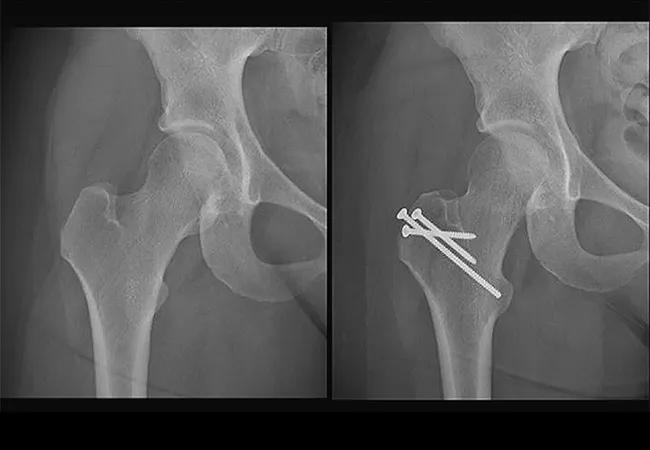

A 21-year-old female presented to Cleveland Clinic’s Hip Preservation Center reporting a restricted range of motion and progressive pain in her right hip. She was involved in a motor vehicle collision and experienced a dislocation of the femoral head. She had sustained a Pipkin-type fracture that went on to form a malunion of the proximal head-neck junction.

Her anatomy was otherwise preserved in terms of quality of cartilage and bony morphology, explains Atul Kamath, MD, Director of the Hip Preservation Center and staff surgeon in the Orthopaedic and Rheumatologic Institute. He had originally planned to manage treatment with surgical dislocation.

At the time of surgery, he noted that the Pipkin area of the fracture, the femoral head, was not viable for grafting back to the donor site. He instead performed an osteoarticular transfer system (OATS) procedure, utilizing an autograft from the patient’s femoral head-neck junction to perform a cartilage transplant.

Elaborating on the OATS procedure, Dr. Kamath says: “Plugs of cartilage were used for mosaicplasty of the femoral head and then any irregularities were filled in with juvenile cartilage cells to perform a Highland cartilage restoration of the significant cartilage injury to the femoral head.”

Postoperative images revealed adequate healing of the recipient site on the femoral head as well as preserved cartilage within the hip. At the time of the latest follow-up, the patient reported excellent hip function and symmetric hip range of motion.